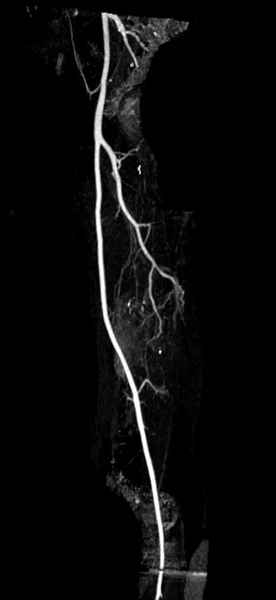

Для предупреждения кровотечения во время рассверливания, за день до операции провели эмболизацию сосудов питающий метастаз. http://radiology.rsnajnls.org/cgi/reprint/150/3/673.pdf (7-11, 12-15-16)

С минимальным рассверливанием и ретроградным методом провели остеосинтез бедра 12 мм гвоздем. (17-20)

Кровопотеря во время операции меньше 100 мл.